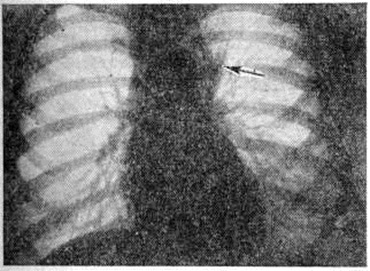

При определённых условиях проводят дополнительные исследования — томографию органов грудной клетки (смотри полный свод знаний Томография), нижнюю кавографию (смотри полный свод знаний), трепанобиопсию (смотри полный свод знаний), лапаротомию со спленэктомией (при подозрении на поражение органов брюшной полости). Из числа вспомогательных исследований применяют скелетную сцинтиграфию (смотри полный свод знаний), сканирование печени и селезёнки (смотри полный свод знаний Печень, радиоизотопное исследование; Селезёнка, рентгенорадиологическое исследование), некоторые биохимический исследования крови, например, определение содержания в сыворотке крови кальция и мочевой кислоты, определение способности к развитию аллергической реакции гиперчувствительности замедленного типа. При рентгенологическое исследовании органов грудной клетки при Лимфогранулематоз может определяться расширенная срединная тень (рисунок 8), чаще в верхнем и среднем отделах, обусловленная увеличением трахеальных, трахеобронхиальных и бронхопульмональных лимфатических, узлов. В зависимости от поражения различных групп лимфатических, узлов срединная тень может быть симметричной или асимметричной. При диффузно-инфильтративной форме Лимфогранулематоз лёгких определяется нечёткость контуров на месте прорастания узла в ткань лёгкого, радиарная тяжистость, которая теряется по мере удаления от корня. Очаговые формы Лимфогранулематоз лёгких имеют обычно однородную структуру затемнения: в одних случаях очаги чётко очерчены и напоминают метастазы опухоли, в других — имеют вид пятнистых теней с расплывчатыми контурами (рисунок 9). При мелкоочаговой форме Лимфогранулематоз лёгких рентгенологически определяется большое число мелких различной формы и плотности изолированных очагов, которые располагаются в одном или симметрично в обоих латинское полях и дают картину, сходную с карциноматозом лёгких. Диагностика, определение объёма и протяжённости поражения забрюшинных лимфатических, узлов осуществляются с помощью ангиографии и лимфографии (смотри полный свод знаний), особенно в сочетании с флебографией (смотри полный свод знаний). На лимфограммах чаще всего удаётся обнаружить увеличение теней лимфатических, узлов (рисунок 10) с сохранёнными ровными, чёткими контурами, а также изменение структуры узлов, которая становится неоднородной, крупнозернистой, иногда «пенистой». В приносящих лимфатических, сосудах отмечается сужение просветов и образование коллатералей. При Лимфогранулематоз желудочно-кишечные тракта с эндофитный формой поражения наблюдаются неравномерность заполнения и прохождения контрастной взвеси, изменение формы просвета или деформация поражённого органа, ригидность стенок, сглаженность рельефа слизистой оболочки. Реже выявляются дефект наполнения или дефект по контуру, а также изменение рельефа слизистой оболочки. При экзофитных формах дефект наполнения определяется чаще, нарушение проходимости и деформация органа встречаются главным образом при опухолях больших размеров (рисунок 11). В начальных стадиях Лимфогранулематоз тонкой кишки рентгенологически определяются неравномерное продвижение и комкование контрастной взвеси, наличие спастически сокращённых сегментов и дефектов наполнения, исчезновение характерного, например, для тощей кишки так называемый перистого рельефа слизистой оболочки. По мере прогрессирования процесса наблюдается дальнейшее утолщение складок с образованием подушкообразных выбуханий, просвет кишки суживается, стенки её становятся ригидными, замедляется продвижение контрастной взвеси. Для уточнения распространённости процесса в брюшной полости применяются мезентерикография, спленопортография (смотри полный свод знаний) и целиакография (смотри полный свод знаний). На ангиограммах при этом выявляются краевые дефекты наполнения, сдавление и смещение сосудов, супрастенотическое расширение их, развитие коллатералей и другие изменения, косвенно указывающие на увеличение лимфатических, узлов. При рентгенологическое исследовании скелета определяются изменения структуры костной ткани, которые характеризуются сочетанием остеокластических продуктивных процессов. Остеокластические изменения могут иметь вид солитарных очагов с нечёткими и неровными контурами или довольно чётко очерченных очагов с узким склеротическим ободком. Иногда при Лимфогранулематоз наблюдается множественная мелкоочаговая деструкция кости, поражённый участок которой приобретает характерный ноздреватый вид. Периостальные реакции чаще отсутствуют, однако при Лимфогранулематоз описаны отдельные случаи периостозов токсического характера типа Мари—Бамбергера (смотри полный свод знаний Бамбергера — Мари периостоз). Лечение. Для лечения Лимфогранулематоз применяют лучевую терапию, различные противоопухолевые цитостатические средства и в части случаев — оперативные методы. Выбор ведущего метода лечения определяется, в первую очередь, стадией болезни: при I, II и IIIA стадиях предпочтение отдаётся радикальной лучевой терапии, а при IIIБ и IV стадиях — химиотерапии. Лучевая терапия Лимфогранулематоз основана на использовании биологический действия ионизирующего излучения (смотри полный свод знаний). Применяется паллиативная (локальная) и радикальная лучевая терапия (смотри полный свод знаний). При локальной лучевой терапии проводится облучение выявленного очага поражения с паллиативной целью; радикальная лучевая терапия направлена, кроме того, и на области вероятного распространения патологический процесса, преследует цель радикального воздействия на все очаги Лимфогранулематоз до стойкого клинические, выздоровления. Лучевая терапия Лимфогранулематоз противопоказана при выраженных симптомах интоксикации, анемии, лейкопении, тромбоцитопении, кахексии, активных формах туберкулёза и лучевых повреждениях кожи и подкожной клетчатки, вызванных проводившимся ранее облучением. Лучевая терапия Лимфогранулематоз проводится главным образом с помощью гамма-терапевтических аппаратов (смотри полный свод знаний Гамма-аппараты), в которых источником излучения служит радиоактивный нуклид 60Со, и электронных ускорителей. Индивидуальное планирование облучения разрабатывается с учётом стадии и морфологический типа Лимфогранулематоз, возраста и пола больного, локализации очагов поражения, скорости прогрессирования процесса и наличия сопутствующих заболеваний. Выбор полей облучения, их размеры, форма и локализация устанавливаются на основании данных рентгенологическое и ангиографического исследований. Радикальная лучевая терапия локализованных форм Лимфогранулематоз проводится в двух технических вариантах — многопольном и крупнопольном (рисунок 12). Многопольный вариант лучевой терапии предусматривает последовательное облучение участков поражения и зон возможного распространения процесса. При этом расстояние между смежными полями должно соответствовать геометрическим границам пучков с таким расчётом, чтобы соседние пучки (выше и нижележащих полей) перекрещивались на уровне мишени. При облучении лимфатических, узлов средостения и забрюшинного пространства с задних полей спинной мозг экранируется свинцовыми блоками до II поясничного позвонка. Крупнопольный вариант облучения проводится с двух противолежащих мантиевидных полей — переднего и заднего — с экранированием индивидуально подобранными фигурными блоками лёгких, головок плечевых костей, гортани (при облучении спереди) и спинного мозга (при облучении сзади). Верхнее мантиевидное поле включает все наддиафрагмально расположенные лимфатических, узлы. При облучении спереди — верхняя граница поля облучения проецируется на уровне края нижней челюсти при запрокинутой назад голове, нижняя — на уровне мечевидного отростка; при облучении сзади нижняя граница поля облучения обычно находится на уровне X — XI грудных позвонков. При крупнопольном облучении исключается опасность появления так называемый горячих и холодных зон на границе соседних полей, сокращается продолжительность курса лучевого лечения. Лимфатических, узлы, расположенные ниже диафрагмы, облучают обычно с двух крупных противолежащих полей, имеющих форму, напоминающую перевёрнутую букву «у», однако крупнопольное облучение тяжело переносится больными из-за быстро возникающих диспептических расстройств и угнетения кроветворения. Поэтому с целью облучения поддиафрагмальных лимфатических, узлов обычно используют многопольное облучение в два этапа: на первом этапе воздействию ионизирующего излучения подвергаются забрюшинные лимфатических, узлы и селезёнка, на втором этапе — подвздошные, паховые и бедренные лимфатических узлы. При IA и IIA клинические, стадиях Лимфогранулематоз некоторые авторы рекомендуют подвергать облучению все основные отделы лимфатических, системы; по мнению других авторов, в этих стадиях процесса достаточно облучение смежных с очагами Лимфогранулематоз областей лимфатических, системы. При IБ, IIБ и IIIA стадиях проводится лучевая терапия всех отделов лимфатических, системы по обе стороны диафрагмы (в IIIБ стадии — в сочетании с химиотерапией). Суммарная поглощённая доза излучения при лимфогистиоцитарном типе Лимфогранулематоз и нодулярном склерозе в очагах поражения должна составлять не менее 4000 рад за 4—4½ недель лечения, а в зонах профилактического облучения — 3000—3500 рад. При смешанно-клеточном типе и ретикулярном варианте Лимфогранулематоз суммарная поглощённая доза увеличивается в среднем на 1000 рад, что вызвано неблагоприятным клинические, течением заболевания при этих морфологический типах Лимфогранулематоз с частым рецидивированием и тенденцией к генерализации. При лучевой терапии Лимфогранулематоз могут возникать различные лучевые повреждения (смотри полный свод знаний), которые вынуждают иногда прерывать курс лечения, нарушая план облучения. Чаще всего развиваются изменения кроветворной ткани с картиной лейкоцитопении, степень выраженности которой зависит от объёма ткани костного мозга, попадающего в зону облучения. После облучения лимфатических, узлов, расположенных выше диафрагмы, наступает умеренная лейкоцитопения за счёт небольшого уменьшения числа нейтрофилов и более выраженного снижения числа лимфоцитов. При облучении лимфатических, узлов, расположенных по обе стороны от диафрагмы, почти у всех больных содержание лейкоцитов падает ниже 3000 в 1 микролитров крови. В некоторых случаях одновременно с лейкоцитопенией развивается тромбоцитопения, которая, как правило, не сопровождается геморрагическими проявлениями. К числу поздних лучевых осложнений относятся перикардиты, поздние пневмониты, индуративный отёк и фиброз кожи и подкожной клетчатки, гипотиреоз. Редкими осложнениями являются послелучевой поперечный миелит, артериит сосудов головного мозга и почек, лучевой эпителиит полости рта и другие Основными показаниями к применению химиотерапии в качестве ведущего метода лечения Лимфогранулематоз являются IIIБ и IV стадии заболевания, а также такие тяжёлые проявления Лимфогранулематоз, как сдавление верхней полой вены, спинного мозга, общего желчного протока, обильный выпот в полости перикарда и другие Опухолевая ткань при Лимфогранулематоз обладает высокой чувствительностью ко многим противоопухолевым средствам, при клинические, применении которых учитываются некоторые избирательные особенности действия: например, натулап (смотри полный свод знаний) активен при всех локализациях процесса, но особенно при Лимфогранулематоз желудочно-кишечные тракта; винбластин (смотри полный свод знаний), по некоторым данным, более эффективен при Лимфогранулематоз лёгких; циплофосфап (смотри полный свод знаний)— при поражении серозных оболочек и мягких тканей; бруиеомицин (смотри полный свод знаний)— при поражении лёгких, костей и печени; натулан и нитрозометилмочевина (смотри полный свод знаний)— при выраженных симптомах интоксикации и другие Результаты лечения Лимфогранулематоз с помощью противоопухолевых средств улучшились вследствие длительного применения цикловой полихимиотерапии, основанной на сочетании препаратов, относящихся к разным классам соединений и отличающихся по механизму цитостатического действия. По данным Де Вита (V. Т. De Vita) и соавторами, полихимиотерапия по схеме МОРР [эмбихин (мустарген), винкристин (онковин), натулан (прокарбазин) и преднизолон] приводит к ремиссии у 60—80% больных генерализованным Лимфогранулематоз Лечение по схеме МОРР проводится двухнедельными циклами (6 циклов с интервалами в 2 недель между циклами, при этом только первый и четвёртый циклы включают преднизолон). Монохимиотерапия как самостоятельный метод лечения используется только в путём случаях заболевания с симптоматической целью или применяется в качестве так называемый поддерживающего лечения у больных с полными ремиссиями Лимфогранулематоз, полученными в результате радикальной лучевой терапии или полихимиотерапии. Наиболее рациональной многими авторами признана программа лечения Лимфогранулематоз I, II и III клинические, стадий, включающая диагностическую лапаротомию со спленэктомией и комплексную терапию, предусматривающую следующие три этапа: первый этап — 2—6 циклов полихимиотерапии, второй этап — радикальная лучевая терапия, третий этап — поддерживающая химиотерапия. Оперативное лечение используется в части случаев при локальных формах Лимфогранулематоз с целью удаления первичного Лимфогранулематоз желудка и кишечника с последующей профилактической лучевой и химиотерапией. Оперативное лечение Лимфогранулематоз проводится также по жизненным показаниям, например, при перфорации или кровотечении из специфических язв желудочно-кишечные тракта. У больной локальной формой Лимфогранулематоз при наступлении беременности может быть принято решение о её сохранении; в других случаях, таящих большую опасность генерализации процесса, показано прерывание беременности (кроме случаев особой психол. настроенности больной на сохранение беременности). Облучение до родов при наддиафрагмальной локализации процесса может быть только локальным, при поддиафрагмальной локализации Лимфогранулематоз лучевая терапия в период беременности противопоказана. В случаях выраженной интоксикации в период беременности может быть назначено лечение противоопухолевыми препаратами. После родов исключается лактация. Дети, родившиеся у женщин, страдающих Лимфогранулематоз, по данным многих авторов, не имеют наклонности к развитию онкологическое заболеваний. Прогноз зависит от клинические, стадии, наличия общих и биологический признаков активности процесса, морфологический типа Лимфогранулематоз С помощью радикальной лучевой терапии, по данным Каплана и Розенберга (Н. S. Kaplan, S. Rosenberg), а также других авторов, излечения локализованных форм Лимфогранулематоз удаётся достигнуть более чем у 80% больных, а применение полихимиотерапии в случаях генерализованного Лимфогранулематоз сопровождается достижением полных ремиссий у 80% больных, из них у 60 — 70% они сохраняются свыше 10 лет. Многие авторы считают неблагоприятными в прогностическом отношении такие морфологический типы, как лимфоидное истощение и смешанно-клеточный тип, и отмечают благоприятное влияние на результаты лечения и прогноз спленэктомии (смотри полный свод знаний). Трудоспособность больных Лимфогранулематоз зависит от стадии заболевания, эффективности проведённой терапии, возраста и другие По данным ряда авторов, в I, II и IIIА стадиях Лимфогранулематоз при радикальном лечении около 70% больных сохраняют трудоспособность. Летальный исход наступает в период генерализации Лимфогранулематоз Непосредственной его причиной являются кахексия, анемия, интоксикация, легочно-сердечная недостаточность, реже — инфекционные и гнойные осложнения, печёночная недостаточность и амилоид оз. Лимфогранулематоз у детей составляет 12 —15% всех злокачественных новообразований в детском возрасте. Чаще он обнаруживается в возрасте 5—8 лет. По данным ряда авторов, отмечается большая частота заболевания у мальчиков, другие авторы такой особенности не отмечают. Из морфологически, типов у детей обнаруживается главным образом лимфогистиоцитарный тип, реже встречается нодулярный склероз. Клинические, картина в большинстве случаев характеризуется острым началом заболевания с увеличением лимфатических, узлов в области шеи и средостения; к более редким начальным проявлениям Лимфогранулематоз относятся поражения надключичных, подмышечных, паховых и других лимфатических, узлов и внутренних органов. Поражение забрюшинных лимфатических, узлов нередко протекает с выраженным болевым синдромом, который может послужить поводом для ошибочного оперативного вмешательства. В отличие от взрослых, у детей при Лимфогранулематоз не характерны симптомы интоксикации (кожный зуд, высокая температура тела, профузные ночные поты), реже наблюдается эозинофилия, однако у детей, как правило, быстрее происходит генерализация процесса, что некоторые авторы объясняют анатомо-физиологический особенностями лимфоидной ткани в детском возрасте. Лечение Лимфогранулематоз у детей комплексное. В I и II стадиях заболевания проводится радикальная лучевая терапия, в III и IV стадиях ведущим методом лечения является химиотерапия по тем же схемам, которые приняты при лечении Лимфогранулематоз у взрослых, но в соответствующих дозах. При радикальной лучевой терапии локальных форм Лимфогранулематоз, по некоторым прогностическим данным, в подавляющем большинстве случаев наступает полная ремиссия с продолжительностью жизни более пяти лет у 70% больных.